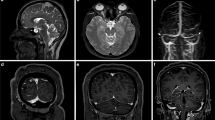

Volumetric measurement of the PSD

To validate our method of measuring volume and compare the characteristics with the volume of the space surrounding the diploic veins, we measured the volume of the PSD in a similar manner. High-signal areas adjacent to the SSS were enclosed by ROIs using the same threshold-based algorithm in 3D Slicer for slices above the superior border of the lateral ventricles on the MSDE T1-weighted transverse images (Fig. 4). To avoid contrast areas other than the PSD and improve reproducibility, measurements were obtained only for high-signal areas within a 1 cm area from the outer edge of the SSS. The high-signal regions in the brain parenchyma and within the skull were manually removed from the ROIs. The volume of the ROIs was calculated and recorded using the functions in 3D Slicer.

Recent studies on the mechanism of brain waste removal have reported the presence of a lymphatic system in the brain [20, 21]. Meningeal lymphatics were identified along the SSS and visualized in human participants by contrast-enhanced MRI [22]. However, later studies suggested that this visualized PSD may not be a true meningeal lymphatic vessel but a bridging space that allows for cerebrospinal fluid-mediated molecular exchange between the meningeal lymphatics and brain tissue [23, 24]. It has been suggested that PSD is involved in the excretion of interstitial fluid and waste products as a downstream pathway of the glymphatic system [25, 26], and its possible association with brain immunity has also been reported [11]. Recently, a significant correlation between the PSD volume and β-amyloid accumulation has been reported [27], increasing the importance of accurate volume measurements of the PSD. In terms of imaging of the PSD, contrast-enhanced fluid-attenuated inversion recovery (FLAIR) and T1-weighted images [22], 3D T1-weighted black-blood MRI [11, 12], and simple T2-weighted images [13] have been used. In this study, the volume of the PSD was measured using contrast-enhanced T1-weighted images with three-axis MSDE performed 4 h after intravenous GBCA injection on 3-T MRI. Our findings regarding the correlation between the PSD volume and age and greater PSD volume in men than in women were consistent with those in previous reports [11,12,13]. The PSD showed an inverse correlation with the space surrounding the diploic veins according to age, suggesting that the PSD may have a complementary function to the space surrounding the diploic veins, although no direct negative correlation was observed. In addition, the PSD volume differed significantly between men and women, regardless of whether it was corrected for intracranial volume, suggesting that the distribution of intracranial waste excretion mechanisms or cerebral immune mechanisms may differ between men and women, and further study is warranted.